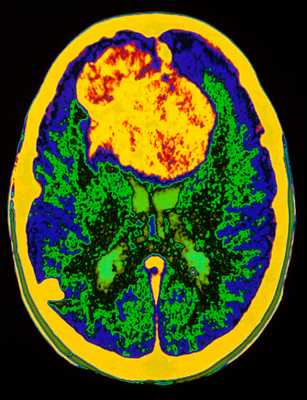

Глиобластома: симптомы, выявляемые с помощью МРТ. Аксиальный срез в режиме Т1 после контрастирования препаратом гадолиния демонстрирует распространенную опухоль правой лобной доли. Изображение предоставлено доктором George Jallo.

МРТ того же пациента. Т2-взвешенное изображение демонстрирует то же поражение, что и на предыдущем рисунке с заметным отеком и смещением срединных структур. Эти находки соответствуют высокой степени злокачественности опухоли.